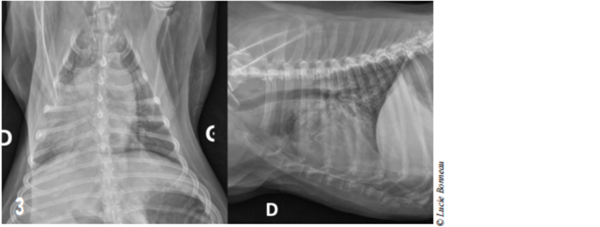

Des radiographies thoraciques (3 vues) constituent le premier examen à réaliser dans l’investigation d’une obstruction des voies respiratoires supérieures. Cela permet d’explorer l’éventuelle présence de lésions pulmonaires, trachéo-bronchiques ou œsophagienne (bronchopneumonie paraspiration (figure 3), œdème pulmonaire post-obstructif, mégaœsophage).

Figure 3 : Radiographies thoraciques : Une densité alvéolaire intéressant principalement l’ensemble des lobes pulmonaires droits est mise en évidence.